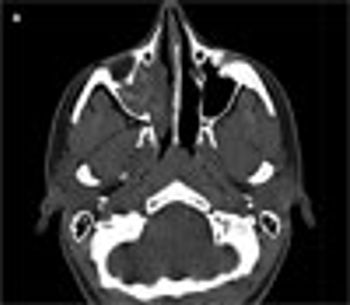

An 18-year-old woman with a history of allergic rhinitis and moderate persistent asthma presented with right-sided nasal congestion of 6 months’ duration. Her symptoms persisted despite her usual allergy medications, allergen immunotherapy, and 2 courses of antibiotics. A sinus CT scan showed complete opacification of the right maxillary sinus with increased attenuation of the mucin. Allergic fungal rhinosinusitis was suspected, and an otolaryngologist was contacted.